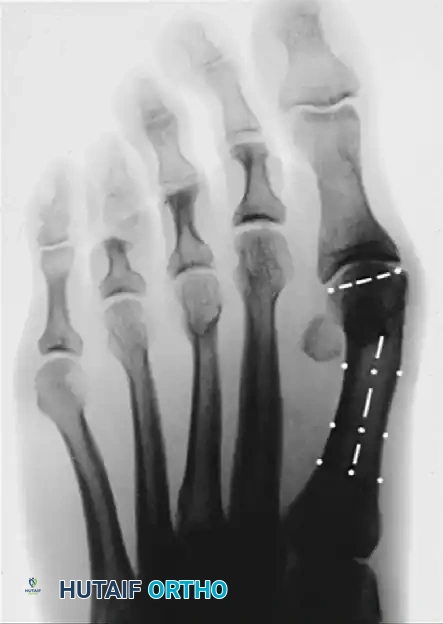

Standard weight-bearing anteroposterior (AP), lateral, and sesamoid axial radiographs are mandatory. Surgical decision-making relies heavily on precise angular measurements.

Image

Key Radiographic Parameters

• Hallux Valgus Angle (HVA): The angle between the longitudinal axes of the first metatarsal and proximal phalanx. Normal is < 15°.

• Intermetatarsal Angle (IMA): The angle between the longitudinal axes of the first and second metatarsals. Normal is < 9°.

• Distal Metatarsal Articular Angle (DMAA): The angle between the articular surface of the first metatarsal head and the longitudinal axis of the metatarsal shaft. Normal is < 10°. An increased DMAA indicates a congruous joint in a valgus position, necessitating a specific intra-articular or extra-articular corrective osteotomy.